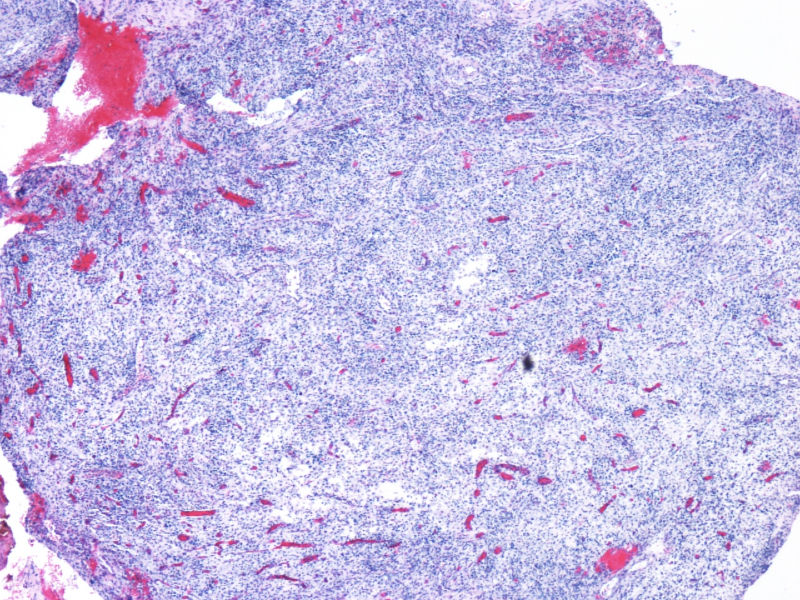

最终诊断为:ALK阳性的间变性大细胞淋巴瘤,淋巴组织细胞变异型。

拿出来的目的:本例始发于骨骼,临床提示脓肿或骨髓瘤,ALK阳性但EMA阴性,细胞毒只有一个标记阳性,本例CD4不阳性。因为CD30和CD15均有非肿瘤细胞阳性的情况,所以对于这个骨骼病例,细胞少而退变,因此最初没有信心诊断,但ALK一般不在非肿瘤细胞内阳性表达,所以最终还是诊断了ALCL。

ALK阳性ALCL发病年龄,发病部位,细胞形态可以非常广泛。西方国家统计男女比例为1.5:1,主要是40岁以内,尤其是儿童青少年多发。本例46岁女性,流行病学应少见的女性发病时段;

如金老师所言原发于骨也少见,如标题所显示:“临床骶骨脓肿?”表现为骨脓肿恐怕更少,综合以上所以本例的确特殊;

形态学hallmark 细胞显示不是很清晰,大的肿瘤细胞如果在ALCL和HL之间选择可能不容易,但HL的肿瘤细胞形态学特点的范围比较狭窄,而ALCL可能具有更广泛的形态学范围,细胞大小形态以及典型hallmark cell的多少有时很难确定。如果只看HE,觉得ALCL的可能会安全一点,当然我个人经验不足,可能理解得比较肤浅。